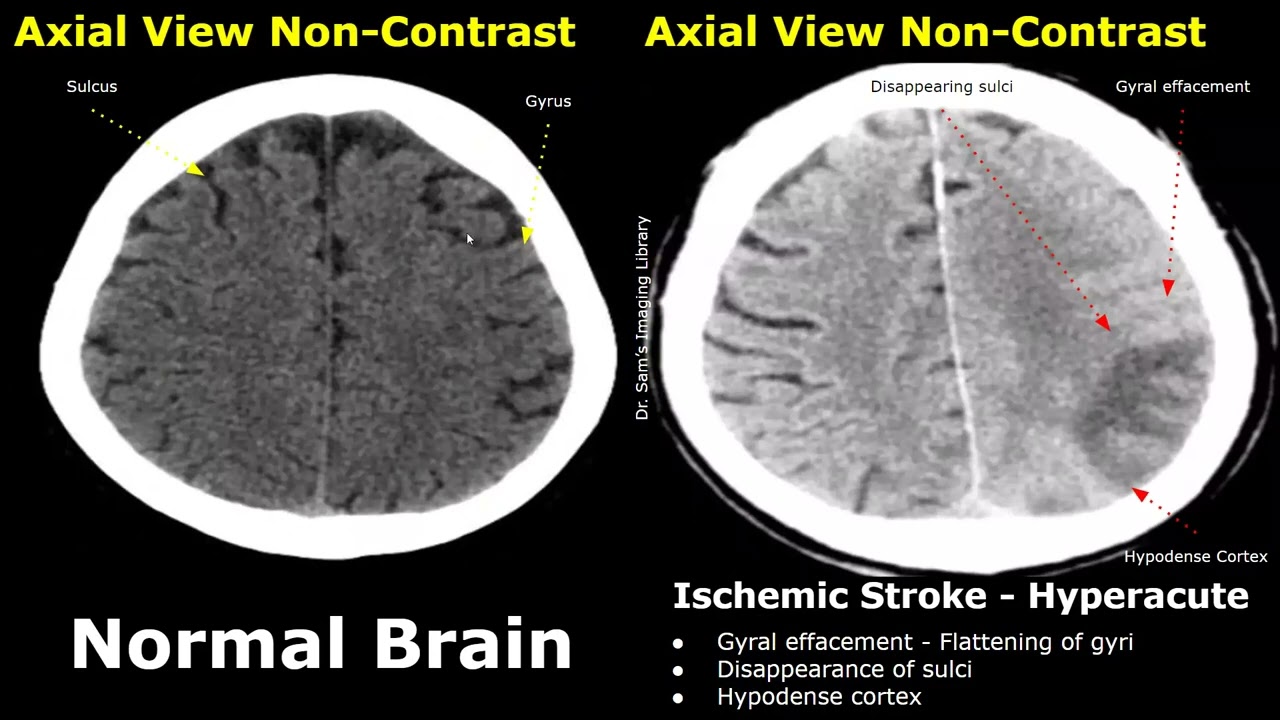

MRI Basics